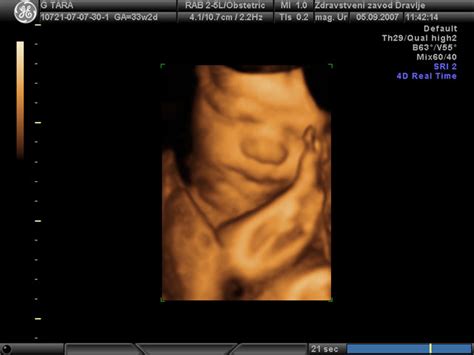

- Ultrazvočni pregled med 18. in 20. tednom nosečnosti: Ta podroben ultrazvočni pregled, pogosto imenovan tudi morfološki ultrazvok, omogoča natančen vpogled v anatomijo ploda. Preverijo se razvoj vseh organov, okončin, prepoznavajo se morebitne strukturne nepravilnosti in določi se spol otroka.